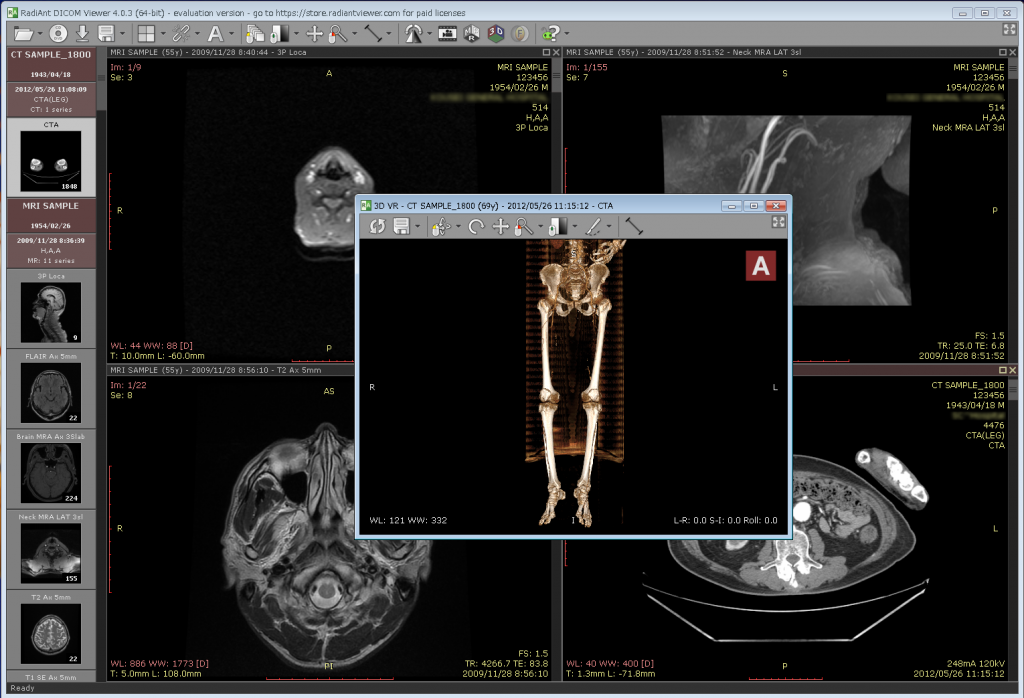

Dicom Viewer RadiAnt

DICOM通信機能が実装されて、Windows 10対応の世界最安、高機能DICOMソフトと謳われている「RadiANT DICOM viewer」を試してみました

Dicom Server「Conquest DICOM software」とのDICOM通信接続も問題なく軽快です

こんな感じ↓

DICOM通信機能が実装されて、Windows 10対応の世界最安、高機能DICOMソフトと謳われている「RadiANT DICOM viewer」を試してみました

Dicom Server「Conquest DICOM software」とのDICOM通信接続も問題なく軽快です

こんな感じ↓